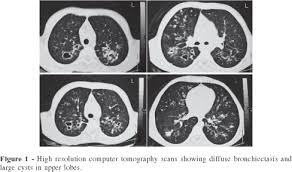

/ Cystic Fibrosis Ct / Accessmedicine S Image Of The Week Ct Findings In Cystic Fibrosis Accessmedicine Network : Cystic fibrosis (cf) is a genetic disease that affects your lungs, pancreas, and other organs.

Cystic Fibrosis Ct / Accessmedicine S Image Of The Week Ct Findings In Cystic Fibrosis Accessmedicine Network : Cystic fibrosis (cf) is a genetic disease that affects your lungs, pancreas, and other organs.

Cystic Fibrosis Ct / Accessmedicine S Image Of The Week Ct Findings In Cystic Fibrosis Accessmedicine Network : Cystic fibrosis (cf) is a genetic disease that affects your lungs, pancreas, and other organs.. Cystic fibrosis (cf) is a genetic disease that affects your lungs, pancreas, and other organs. Read about the symptoms, causes and treatments. Cystic fibrosis is an inherited disease of the exocrine glands affecting primarily the gastrointestinal and respiratory systems. Cystic fibrosis | care guidelines for nutrition management. Care guidelines for nutrition management.